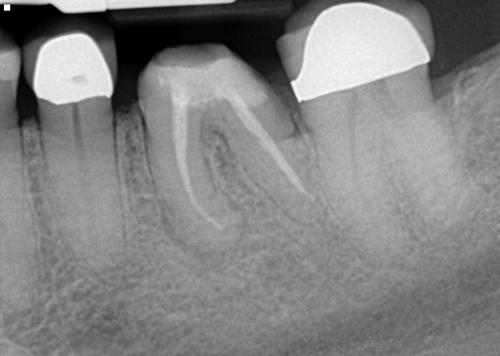

Being able to see the number and shape of the canals accurately prior to treatment is the desire of any clinician who performs endodontics. Research suggests that, due to improved diagnostic accuracy, the final treatment plan may change in up to 50% of endodontic cases if CBCT is used rather than traditional 2D imaging.14,15 The question of whether or not a patient has an MB2 canal can be answered prior to opening the access preparation (Figure 4 and Figure 5). Visualizing single canals that bifurcate in the apical or middle third of the root or those that merge to a single apical opening can help clinicians to understand their instrumentation needs in advance. In addition, the ability to measure the length and shape of a canal planned for instrumentation prior to utilizing an apex locator helps to confirm any measurements obtained by other means. It should also be noted that the ability to see a pathosis in 3 dimensions and to involve the patient in understanding his or her condition prior to any decision-making allows for definitive treatment planning. In fact, many patients have pathoses associated with teeth that are asymptomatic that remain unknown to them until they are visually presented with the evidence (Figure 6).

(4.) In a CBCT image axial view, the MB1 and MB2 canals are readily visible in tooth No. 14, and in the coronal view, these two separate canals can be seen to merge into a single apical opening.

Figure 4

(5.) In a CBCT image axial view, the MB1 and MB2 canals are readily visible in tooth No. 14, and in the coronal view, these two separate canals can be seen to merge into a single apical opening.

Figure 5